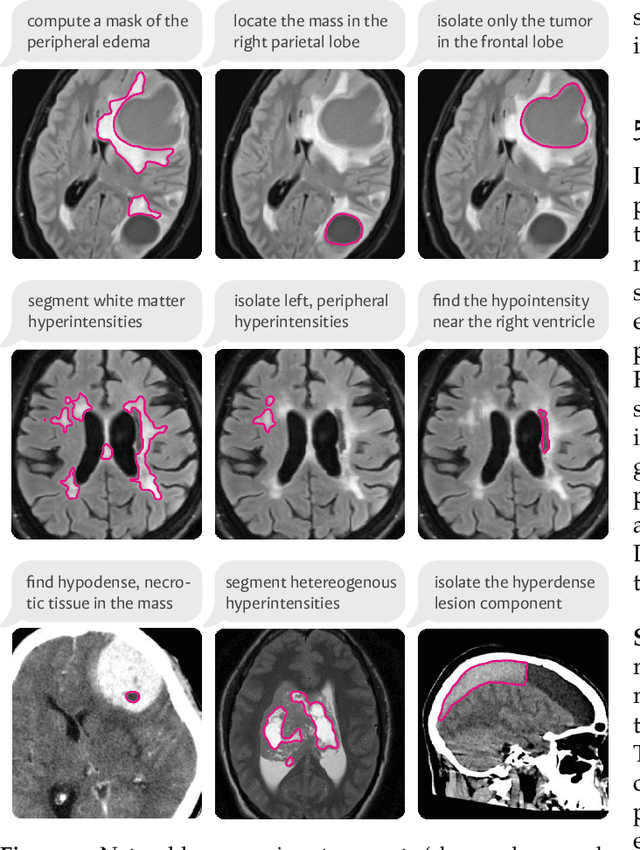

We present VoxelPrompt, an agent-driven vision-language framework that tackles diverse radiological tasks through joint modeling of natural language, image volumes, and analytical metrics. VoxelPrompt is multi-modal and versatile, leveraging the flexibility of language interaction while providing quantitatively grounded image analysis. Given a variable number of 3D medical volumes, such as MRI and CT scans, VoxelPrompt employs a language agent that iteratively predicts executable instructions to solve a task specified by an input prompt. These instructions communicate with a vision network to encode image features and generate volumetric outputs (e.g., segmentations). VoxelPrompt interprets the results of intermediate instructions and plans further actions to compute discrete measures (e.g., tumor growth across a series of scans) and present relevant outputs to the user. We evaluate this framework in a sandbox of diverse neuroimaging tasks, and we show that the single VoxelPrompt model can delineate hundreds of anatomical and pathological features, measure many complex morphological properties, and perform open-language analysis of lesion characteristics. VoxelPrompt carries out these objectives with accuracy similar to that of fine-tuned, single-task models for segmentation and visual question-answering, while facilitating a much larger range of tasks. Therefore, by supporting accurate image processing with language interaction, VoxelPrompt provides comprehensive utility for numerous imaging tasks that traditionally require specialized models to address.